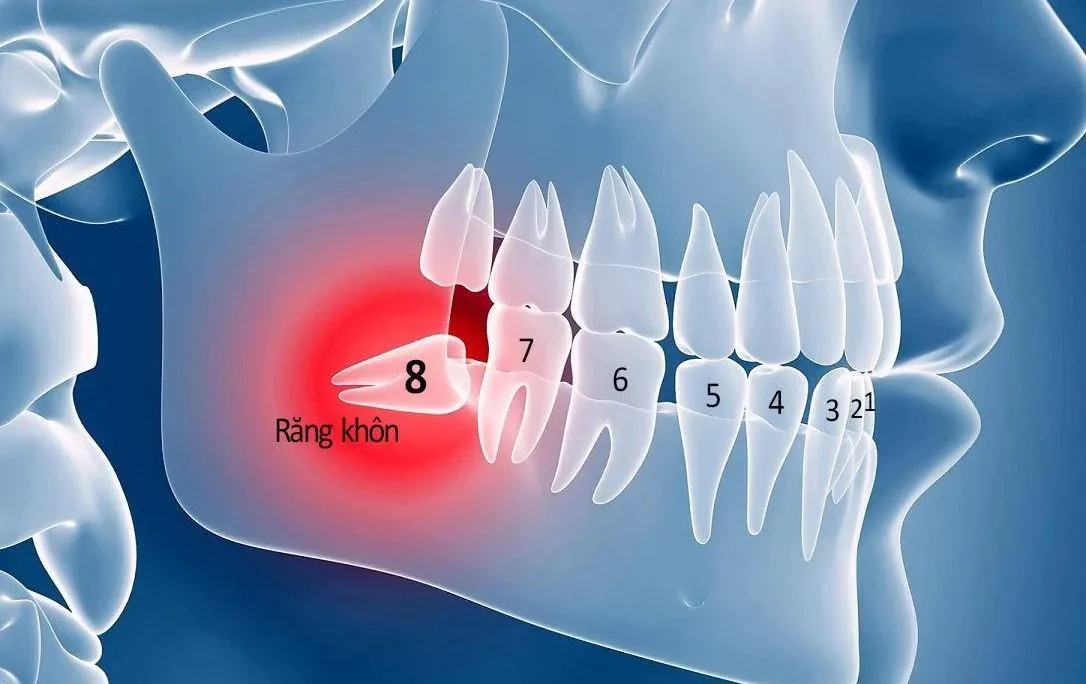

- Mất sự tương thích giữa tỷ lệ răng và xương hàm: Khi răng có kích thước lớn hơn so với không gian có sẵn trong xương hàm, hoặc khi xương hàm không đủ rộng để chứa tất cả các răng. Điều này sẽ dẫn đến tình trạng răng mọc lệch và nhô ra ngoài. Từ đó gây mất thẩm mỹ và không khớp với hàm dưới.

- Bệnh lý về xương hàm: Sự phát triển bất thường của xương hàm. Trong đó bao gồm việc xương hàm trên hoặc dưới phát triển quá mức hoặc không phát triển đủ. Từ đó có thể dẫn đến tình trạng răng hô. Trong những trường hợp nghiêm trọng, cần phải can thiệp phẫu thuật hoặc điều trị chuyên sâu để khắc phục vấn đề này.

Răng hô hàm trên là một trong các kiểu răng hô phổ biến khi răng cửa hàm trên bị đưa ra ngoài. Từ đó gây mất thẩm mỹ và làm mất cân đối cho khuôn mặt. Nguyên nhân chủ yếu của tình trạng này là sự phát triển quá mức của xương hàm trên. Nó khiến phần xương hàm nhô ra bất thường so với hàm dưới. Điều này dẫn đến việc hai hàm trên và dưới không khớp với nhau.

Các kiểu răng hô phổ biến – Hô dưới

Một trong các kiểu răng hô phổ biến khác là hô hàm dưới. Đây là tình trạng mà hàm dưới bị lệch và thường nhô ra ngoài so với hàm trên. Trong một số trường hợp, hàm dưới có thể bị lệch sang một bên (phải hoặc trái). Đây là tình trạng phổ biến do sự phát triển không đồng đều. Đặc biệt là sự không đồng đều của xương hàm dưới.